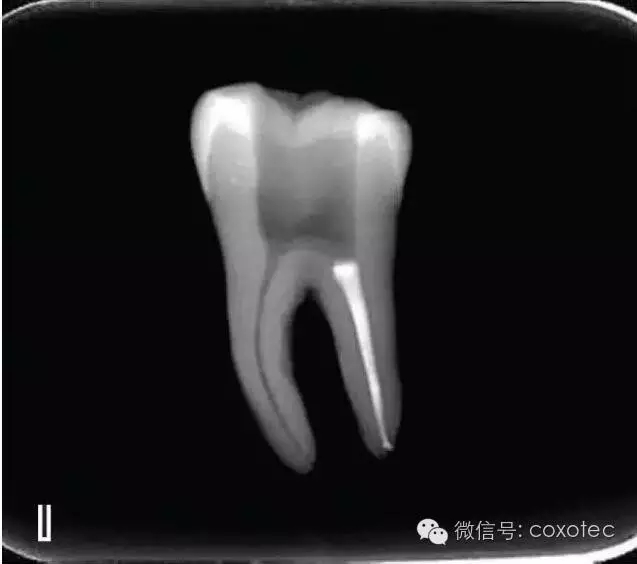

在完成根尖段的充填后,使用熱塑牙膠注射儀對(duì)根管中上段進(jìn)行分層充填,一般分2~3次完成充填,每次充填均使用相應(yīng)直徑大小的垂直加壓器進(jìn)行加壓。拍片確認(rèn)充填效果(圖8)。

A、B.注射儀注射中段熱牙膠

C、D.垂直加壓器加壓

E、F.注射儀繼續(xù)注射上段熱牙膠

G、H.垂直加壓器加壓

I、J.完成根中上段的充填